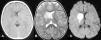

A: en la imagen axial de tomografía computarizada se observa una lesión hipodensa en los ganglios basales derechos con leve efecto de masa en el asta frontal ipsilateral. B: en la secuencia ponderada en T2 en el plano axial, la lesión es hiperintensa y afecta al núcleo caudado, lenticular, brazos anterior y posterior de la cápsula interna. C: en la secuencia potenciada en difusión, se observa una lesión hiperintensa, por la restricción al movimiento del agua debido al edema citotóxico.

La tomografía computarizada craneal sin contraste intravenoso mostró un área hipodensa en los ganglios basales derechos con efecto de masa en el asta frontal ventricular (fig. 1). En las imágenes obtenidas de la resonancia magnética se apreciaba la lesión de los ganglios basales derechos con afectación del núcleo caudado, lenticular, y los brazos anterior y posterior de la cápsula interna; se observaba una restricción al movimiento de las moléculas de agua en la secuencia potenciada en difusión, por el edema citotóxico. Los hallazgos eran compatibles con el diagnóstico de infarto isquémico agudo. El estudio vascular cerebral se realizó con secuencia 3D TOF, donde se identificó una pequeña lesión estenótica de margen irregular en el segmento M1 de la arteria cerebral media (ACM) derecha, que afectaba a la salida de las ramas lenticuloestriadas (fig. 2).